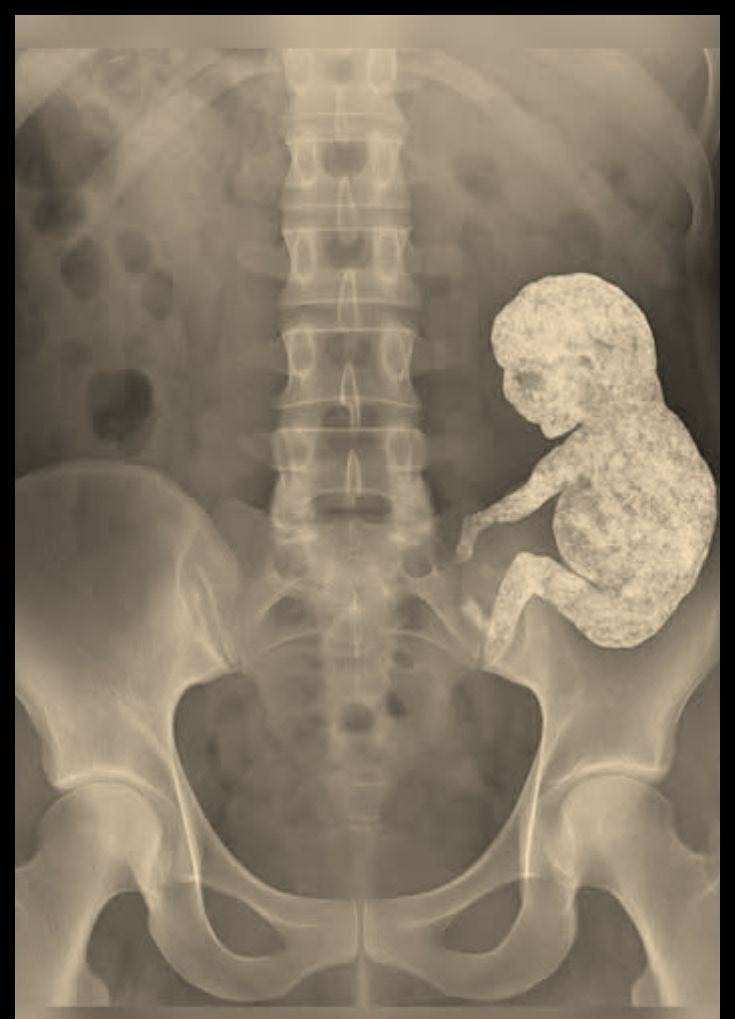

Sur l’écran d’échographie, le médecin se figea. Une masse dure était visible dans l’abdomen de la vieille femme – ronde, entourée de calcium, comme figée dans l’éternité. Un scanner confirma qu’il ne s’agissait pas d’une tumeur. C’était un lithopédion. Un fœtus en pierre.

La lithopédion est un phénomène extrêmement rare, dont même les médecins parlent avec une horreur révérencieuse. Lorsqu’un embryon meurt hors de l’utérus, le corps est incapable de l’expulser. Pour prévenir l’infection, le corps l’enferme dans une coquille de calcium, comme un sarcophage. La nature accomplit l’impossible : elle transforme la mort en pierre.

C’est ainsi que, des décennies plus tard, les chirurgiens prélevèrent soigneusement de son abdomen une petite forme presque parfaite. Un crâne. Des côtes. Un bras minuscule, plié au coude.